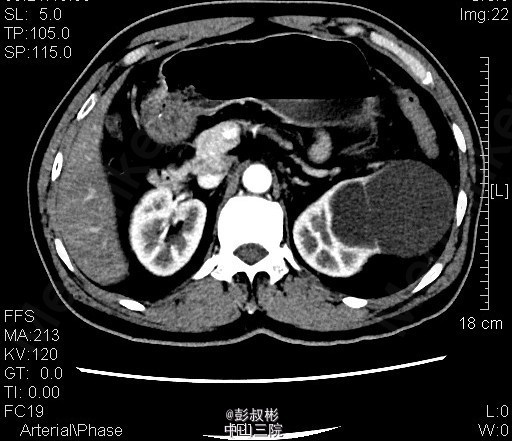

3、查体:腹稍膨隆,无压痛、反跳痛,未触及肿物,双肾区无红肿、隆起,无叩痛,双侧肋脊点、肋腰点无压痛。腹平软,双侧上中输尿管点无压痛,膀胱区无压痛。双侧腹股沟区未触及肿物。 4、CT:双肾多发囊肿,左肾囊肿较大,推压左侧肾盂肾盏。左肾小结石.轻度弥漫性脂肪肝

5、左肾囊肿 6、住院后完善相关检查,查血、尿常规,生化,凝血,心电图,胸片等未见明显异常。CT:双肾多发囊肿,左肾囊肿较大,推压左侧肾盂肾盏。左肾小结石.轻度弥漫性脂肪肝。经术前准备,行单孔腹腔镜下肾囊肿去顶术,手术顺利,术后予预防感染、营养支持等治疗,术后恢复较好,术后病理示:左肾囊肿。